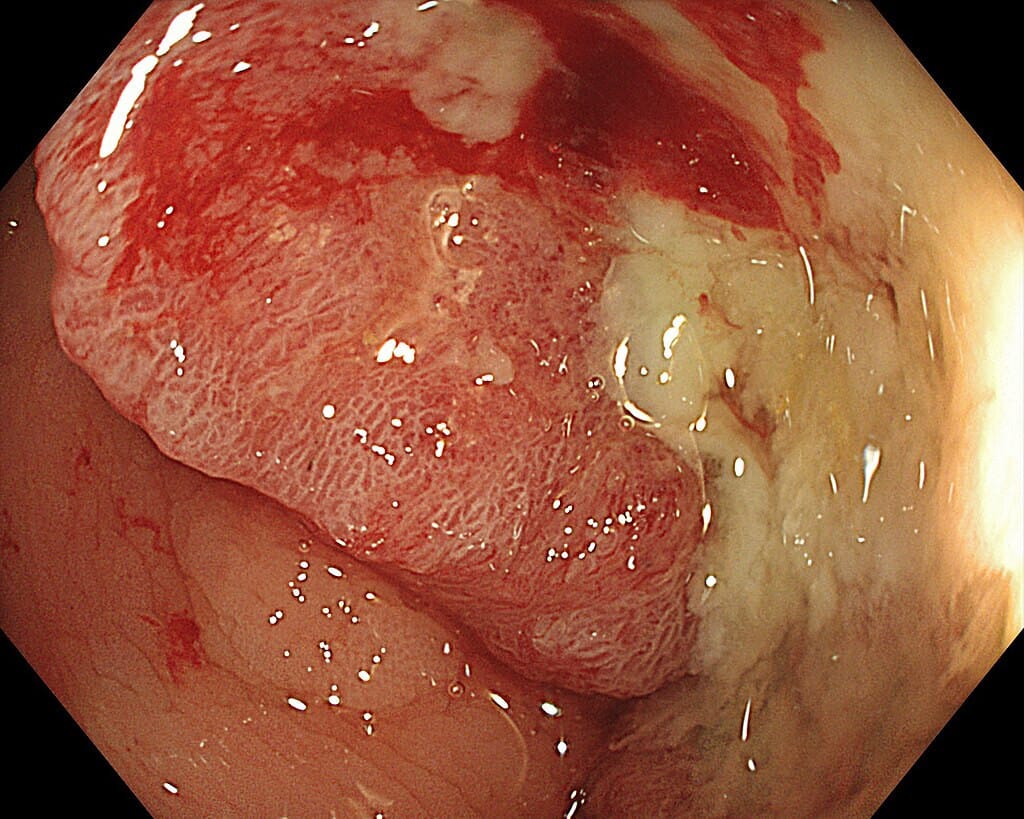

내시경 소견

대장내시경은 병변의 형태를 직접 관찰하고 조직검사를 시행할 수 있습니다.

대장내시경에서 관찰되는 결장암의 소견

🔵 비정상적 돌출 병변

선종성 용종 또는 융기된 종괴가 보이며, 표면이 불규칙하고 출혈이 동반될 수 있습니다.

🔵 궤양성 병변

중앙이 함몰되고 가장자리가 융기된 궤양 형태로, 진행암에서 흔히 보입니다.

🔵 협착성 병변 (Annular type)

장강을 둘러싸듯 좁히는 병변으로, 내시경 통과가 어려운 경우도 있습니다.

🔵 출혈 및 삼출물

조직이 약하고 쉽게 출혈하며, 표면에 백태나 삼출물이 덮인 경우도 있습니다.

🔵 불규칙한 혈관 패턴

정상 점막에 비해 미세혈관 구조가 파괴되고, 비정상적 혈관 증식이 보일 수 있습니다.

By డా. గన్నవరపు నరసింహమూర్తి – Own work, CC0, https://commons.wikimedia.org/w/index.php?curid=167754495